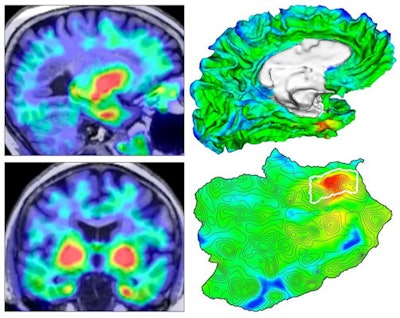

After applying their automated PET analysis method to quantify tau progression in patients with Alzheimer's disease at different stages, a group of researchers led by first author Justin Sanchez and senior author Dr. Keith Johnson of Massachusetts General Hospital (MGH) found that tau signal emerged initially in the rhinal cortex -- independently of beta-amyloid levels -- before it spreads in the brain.

Building on recent work that enabled calculation of molecular PET measurements in tau-vulnerable convolutional temporal lobe anatomy, the researchers developed an automated anatomic sampling method to quantify tau signal on PET exams. They then applied their method to PET exams of 443 adult participants from several observational studies of people with Alzheimer's disease. These patients encompassed a wide range of ages, levels of beta-amyloid burden, and degrees of clinical measurements, according to the researchers.

The investigators found that tauopathy initially emerged near the rhinal sulcus in clinically normal people. In a subset of 104 participants who had longitudinal two-year follow-up data, the researchers also observed beta amyloid-associated spread of tau from this site to the nearby neocortex of the temporal lobe, followed by the extratemporal regions. Furthermore, subsequent elevation of tau in the temporal neocortex was associated with age, beta-amyloid, and apolipoprotein E status.